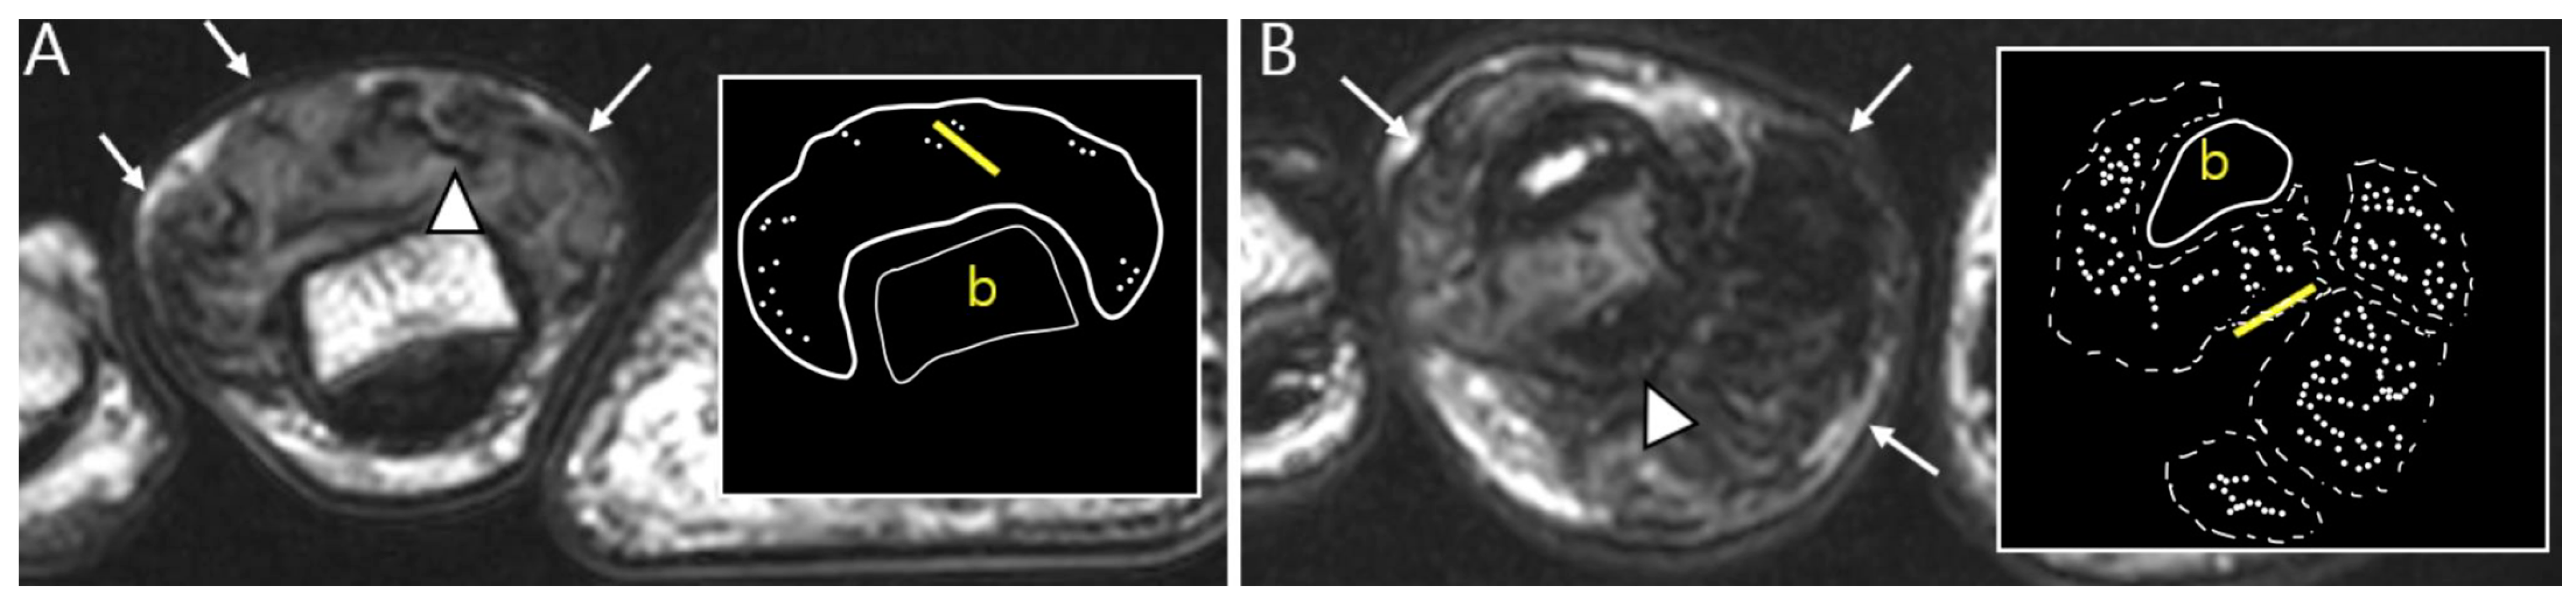

The extra-articular growth of D-TSGCT primarily arises as a result of extra-articular extension of intra-articular D-TSGCT through transcapsular fenestrations (Figure 1 and Figure 3) [31]. However, due to its infiltrative growth pattern, determining the origin is often challenging [32]. Instances of extra-articular D-TSGCT without intra-articular communication are exceedingly rare, and such cases involve the bursa around the knee, such as popliteal bursa (Figure 4) [20,32,33,34,35]. In cases where TSGCTs occur in the digits, they are typically located in extra-articular portion, and it is crucial to differentiate between two subtypes [36]. Jeong et al. [36] conducted a comparison of the MRI morphologic features of TSGCTs in the digits between the diffuse type and localized type. Their findings revealed that D-TSGCTs in digits manifest as multinodular and infiltrative masses without a peripheral capsule. Kim et al. [28] also found that the most sensitive MRI parameter with the highest odds ratio for extra-articular D-TSGCT, which was the lack of peripheral hypointensity (lack of capsule) (Figure 5).

Figure 5.

Nodularity, margin, and peripheral hypointensity between two subtypes. (A) Pathology-proven L-TSGCT of the foot shows that the mass is shown as a single mass with a circumscribed margin (arrows) on axial T2WI. The mass shows the avid peripheral hypointensity (see in box) and encasement of the extensor tendon (arrowhead). (B) Pathology-proven D-TSGCT of the foot shows that the masses contain multiple distinct nodules with an infiltrative margin from the surrounding tissues (arrows) on axial T2WI. The masses show the absent peripheral hypointensity (see box) and encasement of the flexor tendon (arrowhead). Box; b = bone, yellow line = tendon.